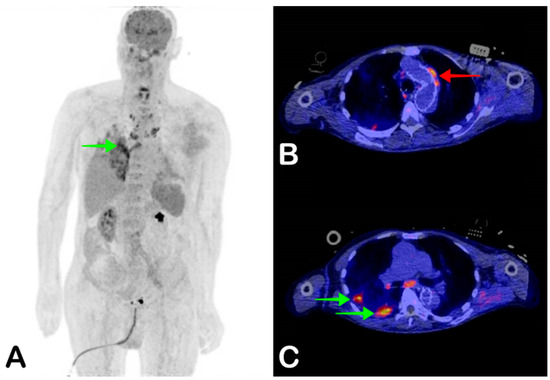

4. White Blood Cell Cintigraphy

- Lauri, C.; Glaudemans, A.W.J.M.; Campagna, G.; Keidar, Z.; Muchnik Kurash, M.; Georga, S.; Arsos, G.; Noriega-Álvarez, E.; Argento, G.; Kwee, T.C.; et al. Comparison of White Blood Cell Scintigraphy, FDG PET/CT and MRI in Suspected Diabetic Foot Infection: Results of a Large Retrospective Multicenter Study. J. Clin. Med. 2020, 9, 1645. [Google Scholar] [CrossRef] [PubMed]